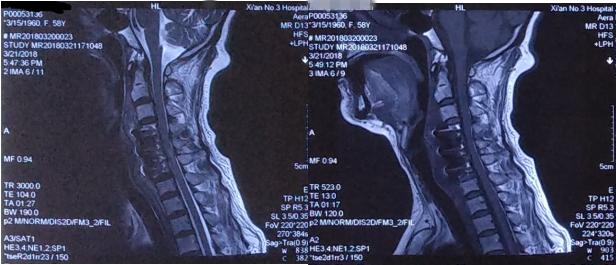

术前颈椎MRI

矢状位MRI提示颈4/5、5/6椎间盘突出,后方脊髓受压变性

轴位MRI提示颈4/5中央型、5/6外侧型椎间盘突出,压迫后方脊髓组织

术后颈椎MRI复查

矢状位颈椎MRI:颈4/5、5/6脊髓前方压迫解除,椎管宽度恢复

轴位颈椎MRI提示颈4/5、5/6突出椎间盘切除,脊髓受压解除